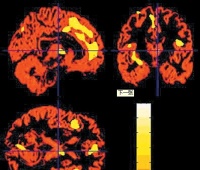

4.PTSD的神经解剖的改变和易感性通过PET研究显示PTSD患者在某些区域脑血流严重减低,包括眶额皮质前扣带回、前额叶正中皮质(Brodmann’sareas29)梭状回/颞叶下皮质而在后扣带回,左皮质下相关区域及运动皮质的激活性增加这些区域与记忆环路有关。PET及功能核磁MRI证实,杏仁核和前旁边缘区对创伤性刺激的反应性增强;而前扣带回和视前区的反应性降低(这些区域与恐惧反应有关)LeDoux(1998)发现,机体的恐惧反应与杏仁核有关杏仁核将学习得到的感觉信息结合到适应反应(搏斗或逃跑)中去,使机体作行动的准备(如心输出量从胃肠道转向肌肉应激激素涌进血流以提供能量)。这些活动发生先于脑的“思维”部分(涉及大脑皮质中的海马)对威胁的估量说明杏仁核在这里起着“拦路抢劫”(hijacked)的作用。因此LeDoux(1998)提出杏仁核是躯体的表达陈述部位,它对任何与创伤匹配的远隔问题,不需要经过大脑皮质察觉和作出决定,就可激活恐惧反应海马负责长期的陈述记忆,并将新的记忆归档(filingaway)。海马与杏仁核有联系,故可以对其进行控制但有两个问题要注意:①从杏仁核到海马的是快速度通道而返回的另一条通道提示海马对杏仁核的制服并不是经常可能的;同样额叶前正中皮质(一个可以抑制杏仁核功能的结构)的减少加强了杏仁核的表达,也就增加了创伤记忆的集中和频发。PTSD病人海马体积减小(Yehuda),可以解释患者的陈述性记忆的缺乏。但是不知这是否发生在遭遇创伤以前?但就是PTSD的易感因素。②(LindaCarroll,2003.7)发现PTSD患者的前扣带回区(AnteriorCingulateCortex,ACC)明显小于正常人群ACC在脑的情感调制过程中起到帮助患者注意到自身或环境的作用,而PTSD患者的ACC功能被削弱但是不能表明PTSD遭遇创伤前ACC就较小,但是一旦发生为PTSD,ACC部分就被侵袭了,这可以帮助我们了解PTSD的患者的临床症状另外脑电图研究也表明:PTSD患者α波减少而β波增加,β兴奋增加超过额叶正中皮质平面和左枕部的区域βII兴奋增加表现在额叶θ波范围超过额叶正中区表明皮质的过度兴奋延长觉醒时间额叶对激活的调节失调,增加θ波兴奋可以帮助解释海马体积的改变说明PTSD患者发生神经生物学的改变。